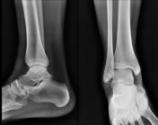

![]() ![]() os subfibulare 上の図は、捻挫した後の足首です。外くるぶしの下に小さな骨片が見られます。ここには、靭帯が付着しておりますので、足首が、緩く不安定になっています。あとから、関節炎や軟骨の変性が起きてきます。これを見逃さず、初期から、しっかりした固定が必要ですね。ほっておくと、下のようになります。 ![]() ![]() inpingement exostosis CT画像では、はっきりしてきます。常に予後を考えた、治療に専念したいものです。 |